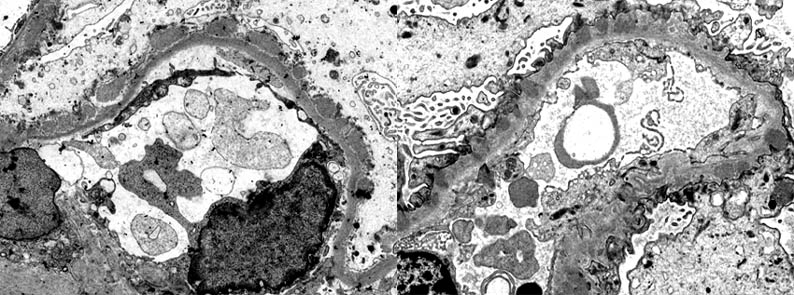

Figure 12a. Left: electron-dense deposits on the outside of the basement membrane, without reaction of this around the deposits: Stage I. Right: deposits surrounded laterally by material similar to that of the basement membrane ("spikes"): Stage II. Original magnification, X4,000. (Images courtesy of Dr. Carlos A, Jiménez).

Figure 12b. Left: Electron-dense deposits are completely surrounded by basement membrane-like material, giving the appearance of being "embedded" within a very thick and irregular basement membrane: Stage III. Right: the glomerular basement membrane is thick and irregular and electron-dense deposits have almost disappeared: Stage IV. Original magnification: left, X4,000, right, X6,000. (Images courtesy of Dr. Carlos A, Jiménez). Note the extensive loss of pedicels in the four previous images.

There are electron-dense deposits in the epithelial aspect (external) of the GBM, between this one and the epithelial cell: subepithelials or epimembranous. These deposits are usually diffuse and homogenously distributed, but they can be, in some cases, irregularly distributed. Spikes are demonstrated as irregular projections of the GBM among the subepithelial deposits; with progression of the disease these projections become longer and surround the deposits incorporating them in a thickened GBM. The deposits are amorphous; the presence of organized deposits must alert of a possible lupus nephritis. These deposits lose their electron density until disappear in the advanced stages of the process. Like in many other diseases with NS, there is a variable loss or effacement of podocyte foot processes. In some cases, more frequently secondary, there are dense deposits in mesangium. (Image of MGN stage II (link) - More EM images (link)